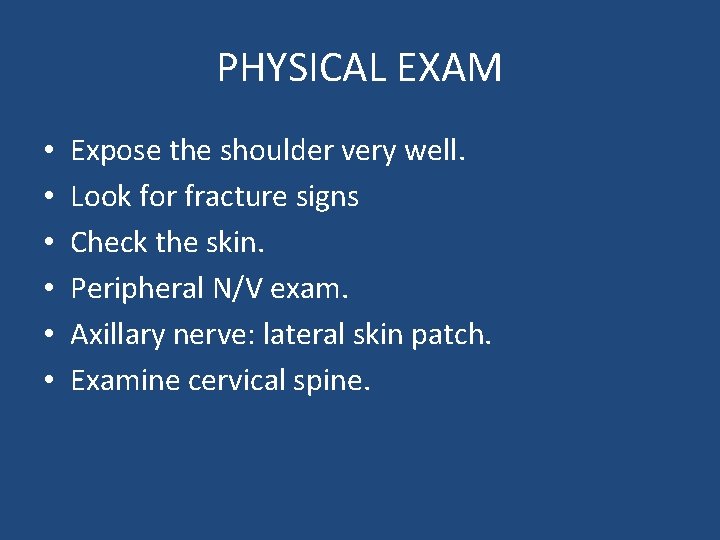

PHYSICAL EXAM • • • Expose the shoulder very well. Look for fracture signs Check the skin. Peripheral N/V exam. Axillary nerve: lateral skin patch. Examine cervical spine.